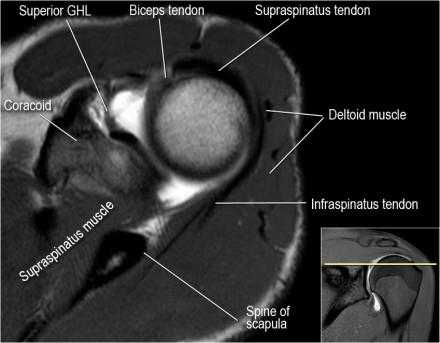

Нормальная анатомия

Нормальная анатомия плечевого сустава в аксиальных изображениях и контрольный список.

- поищите os acromiale, акромиальную кость (добавочная кость, расположенная у акромиона)

- обратите внимание что ход сухожилия надостной мышцы параллелен оси мышцы (это не всегда так)

- обратите внимание что ход сухожилия длинной головки двуглавой мышцы в области прикрепления направлен на 12 часов. Область прикрепления может быть различной ширины.

- обратите внимание на верхние отделы суставной губы и прикрепление верхней плече-лопаточной связки. На данном уровне ищется SLAP-повреждение (Superior Labrum Anterior to Posterior) и варианты строения в виде отверстия под сутавной губой (sublabral foramen - подгубное отверстие). На этом же уровне по задне-боковой поверхности головки плечевой кости визуализируются повреждение Хилл-Сакса.

- волокна сухожилия подлопаточной мышцы, создавая бицепитальную борозду, удерживают сухожилие длинной головки двуглавой мышцы. Изучите хрящи.

- уровень средней плече-лопаточной связки и передних отделов суставной губы. Поищите комплекс Буффорда. Изучите хрящи.

- вогнутость заднебокового края головки плечевой кости не следует путать с повреждением Хилл-Сакса, поскольку это нормальная форма для данного уровня. Повреждение Хилл-Сакса визуализируется только на уровне клювовидного отростка. В предних отделах мы сейчас на урвоне 3-6 часов. Здесь визуализируются повреждение Банкарта и его варианты.

- обратите внимание на волокна нижней плече-лопаточной связки. На данном уровне так же ищется повреждение Банкарта.